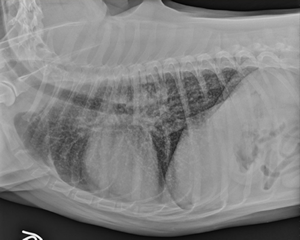

A lateral view radiograph of the thorax is shown. Which of the following is a correct description of the radiologic findings? (You may select only one option.)